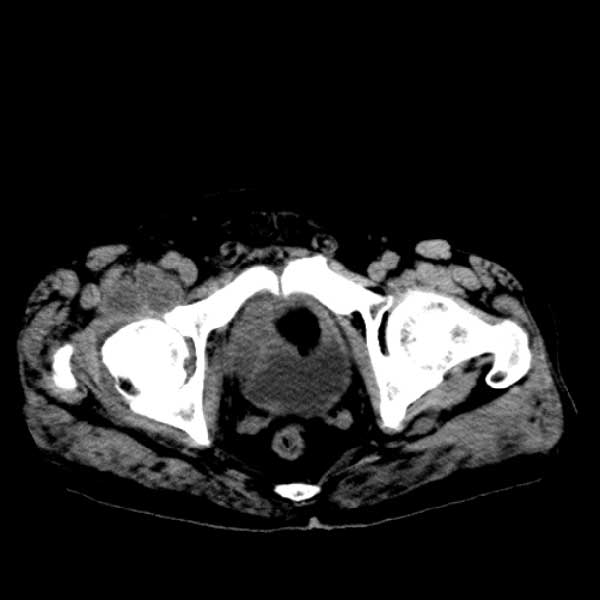

标题: CT13513:男 71 腹部疼痛20余天,近几天高热就诊,骨窗未见异 [打印本页]

标题: CT13513:男 71 腹部疼痛20余天,近几天高热就诊,骨窗未见异

考虑感染性病变可能性大,起源于阑尾?

感染,脓肿形成

考虑为化脓性阑尾炎.脓肿形成.及多肌肉累及.

考虑右侧腰大肌脓肿,向右髂窝、右腹股沟流注。

支持化脓性阑尾炎伴右髂窝脓肿、腰大肌腰方肌脓肿形成。

考虑腹腔及盆腔化脓性炎症,累及右侧髋关节及腹股沟区.

首先考虑化脓性阑尾炎伴腰大肌、腰方肌脓肿,不除外回盲部结核。

回盲部癌待排除。

患者肠镜检查考虑结肠癌,病理证实

患者肠镜检查考虑结肠癌,病理证实。肺部ct可见多发结节,考虑转移